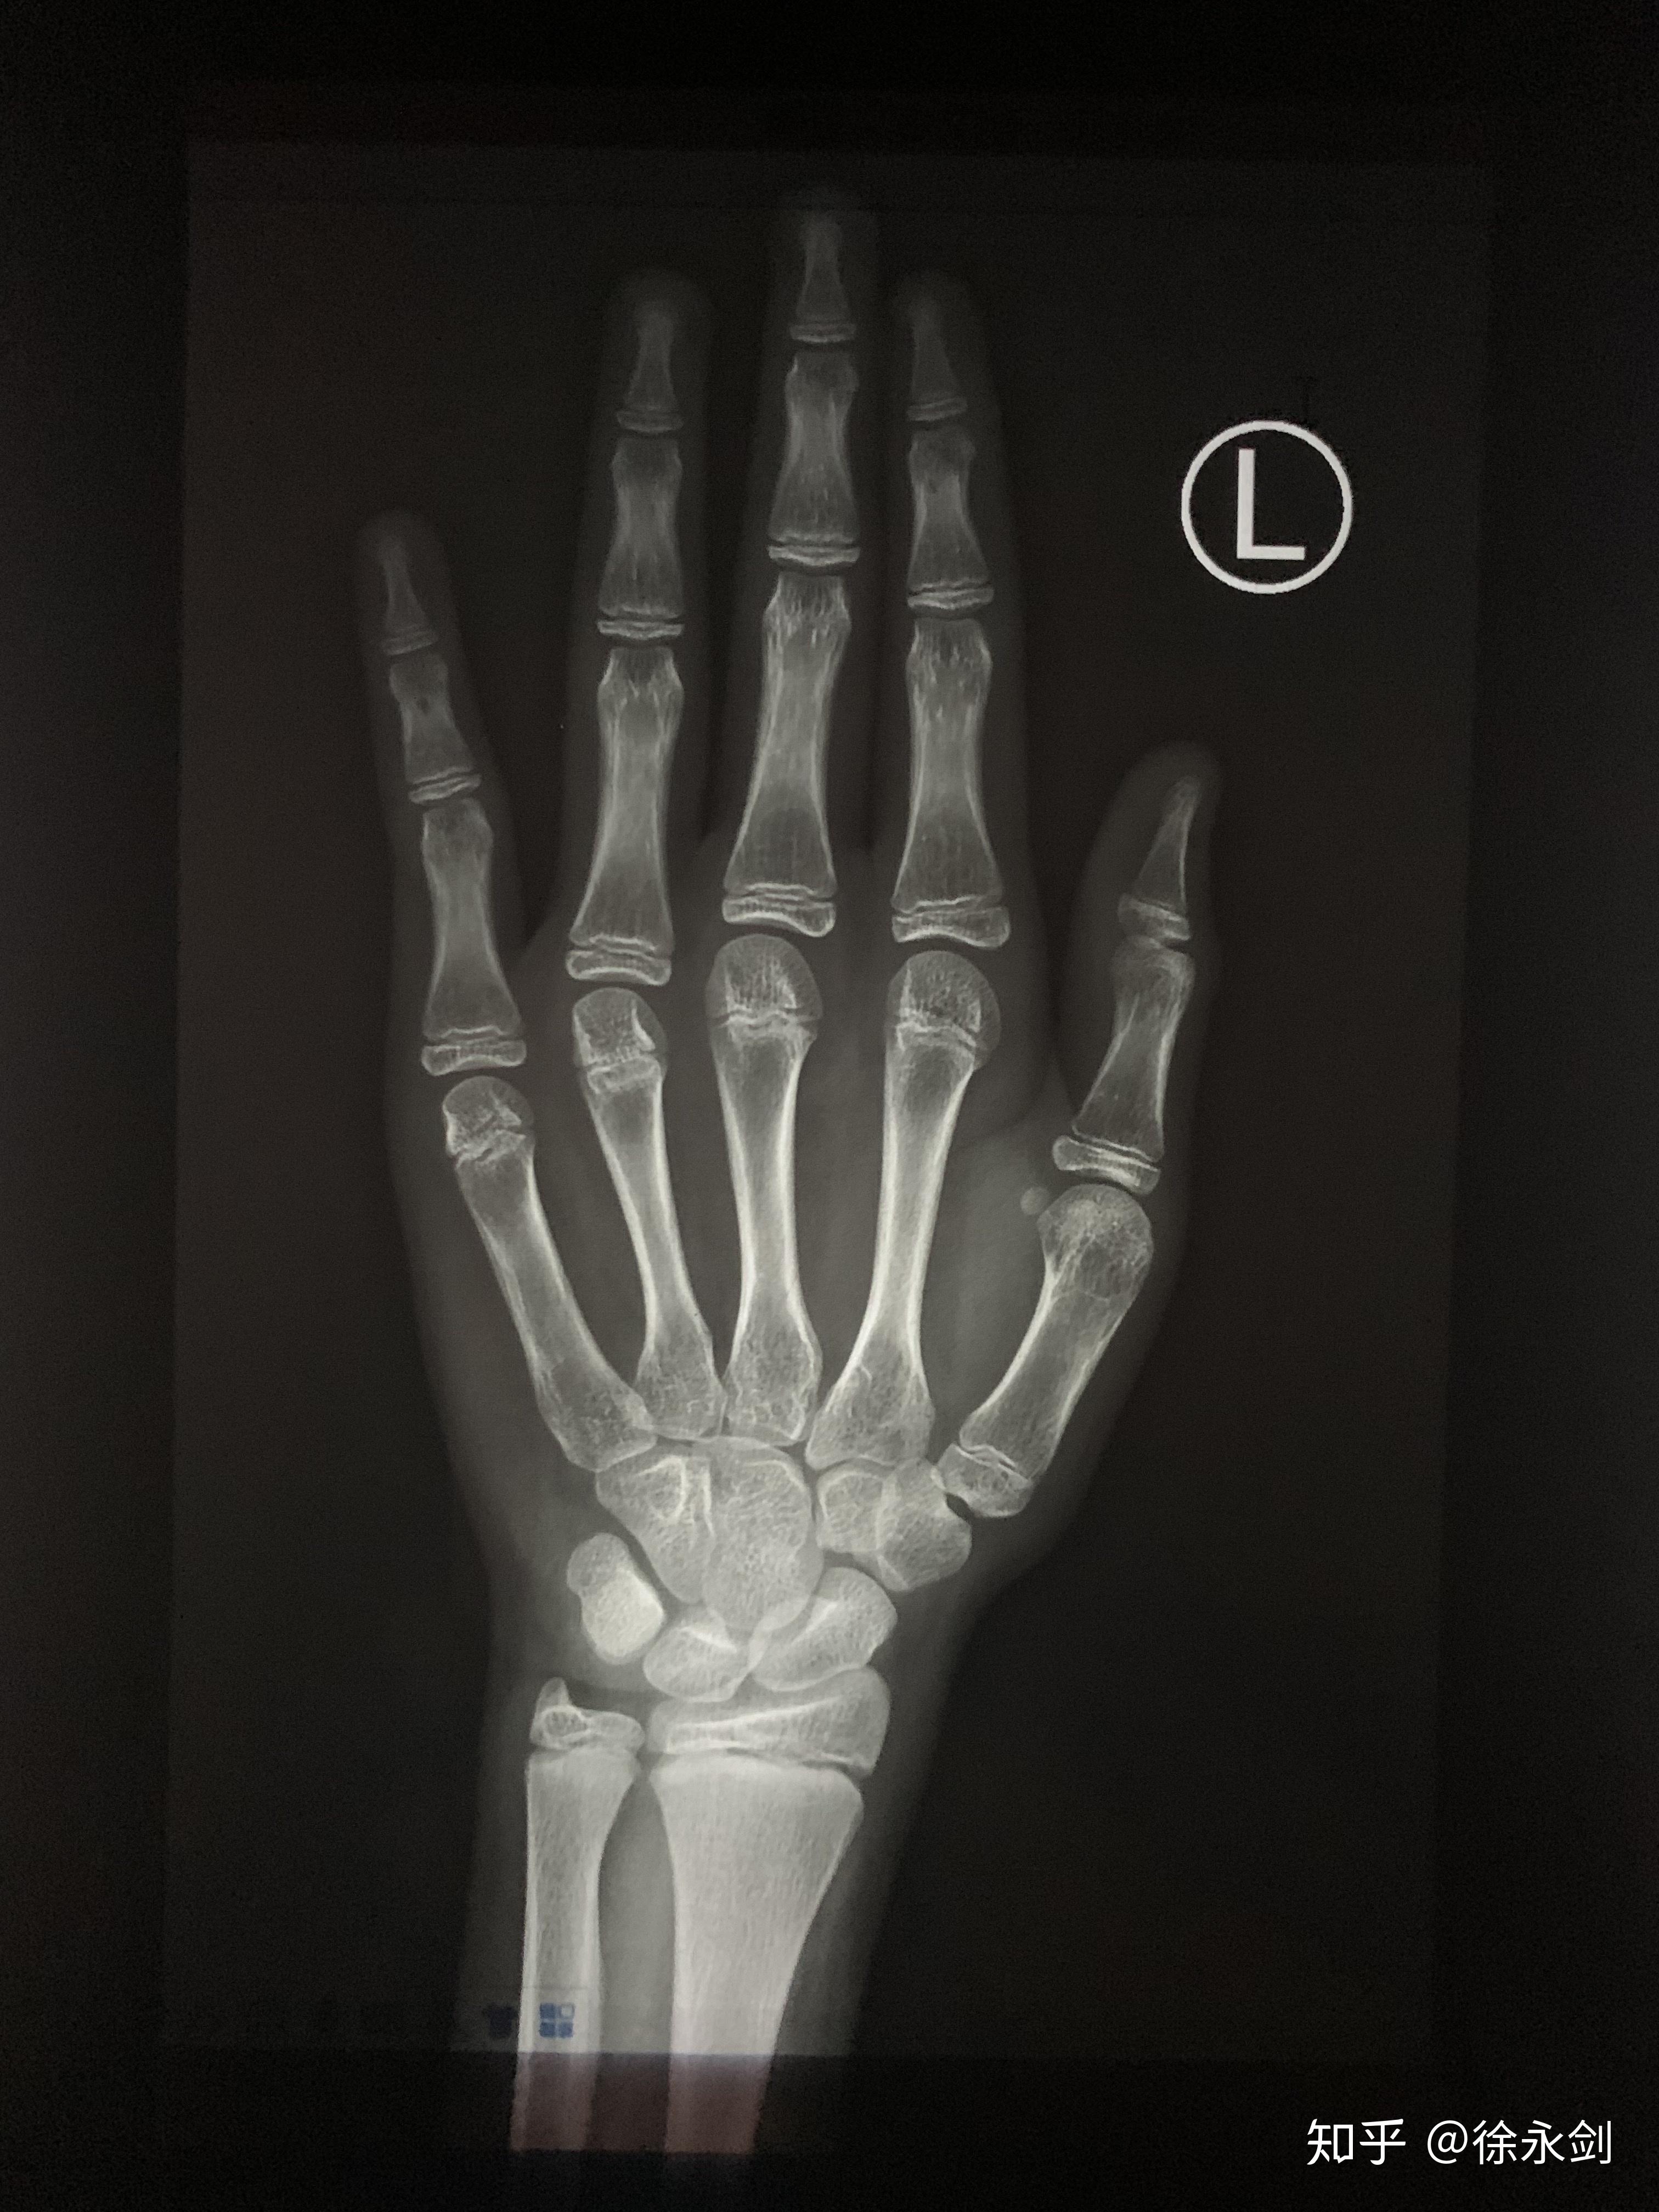

男孩12岁6月与女孩12岁的骨龄片(男孩上图,女孩下图)12.

2岁骨龄,150.1基数预测未来身高158至164.中间值为161.